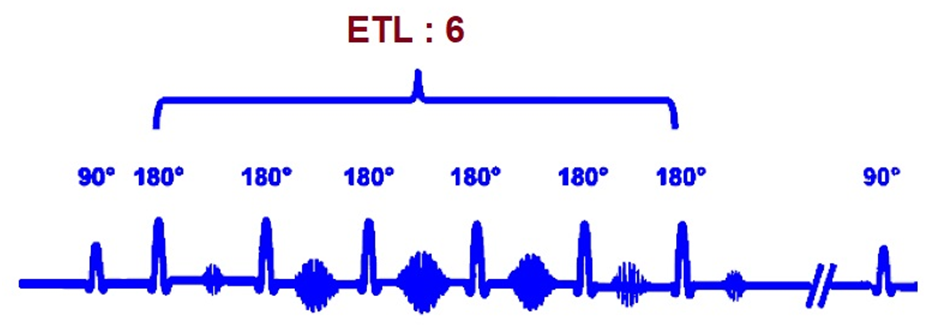

Одним из важных параметров МРТ-изображений является Echo train length (ETL), который, по сути, определяет количество строк К-пространства, заполняемых за одно время повторения TR.

Для ИП типа простого SE (спин-эхо) ETL равен 1, т.к. заполняется одна строка. Для быстрого спин-эха (FSE – Fast SE) с такими же TR и TE этот параметр больше 1 – заполняется по несколько строк сразу. Для UltraFSE и других сверхбыстрых последовательностей – все строки за один TR. Чем выше ETL, тем меньше в итоге времени требуется на получение изображения, но при этом контраст снижается, а шум возрастает. Разумное значение ETL выбирается оператором с учетом задачи и исследуемого органа. Например, для подвижных органов (сердце, легкие, кишечник и т.п.) использование ИП с высоким ETL позволяет снизить влияние движений на резкость слайсов.

Из-за явного влияния на контраст и шум изображений этот параметр полезен как при выборе оптимальных серий, так и при анализе ошибок и устранении выбросов из датасета.